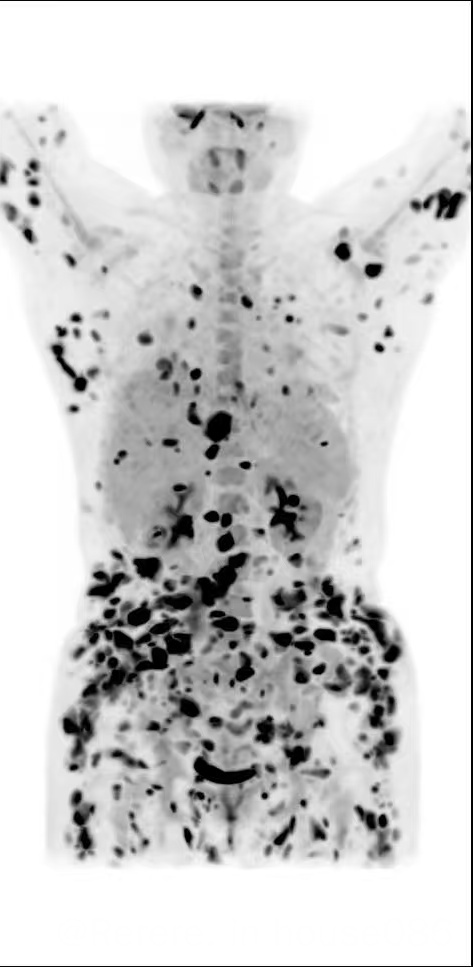

在外院经历了6次的化疗,没有期盼到缓解,肿瘤却疯狂的反扑进展了……全身的皮肤、大脑、胸腹腔、左眼视神经全部失守,望着那满屏黑点的PET CT,眼前的世界一天天暗下去,怀疑自己的人生是否就定格在这黑白画框里……

今天是我重生的75天,顺利康复出院了。PET CT这张照片是我最期盼最爱的一张照片!今天的CR喜报是我和爸爸、妈妈以及弟弟共同打赢的生死契约,也凝结着曹星玉主任、柳喜洋主任、薛松主任、祁大夫及整个医疗团队的智慧与心血。